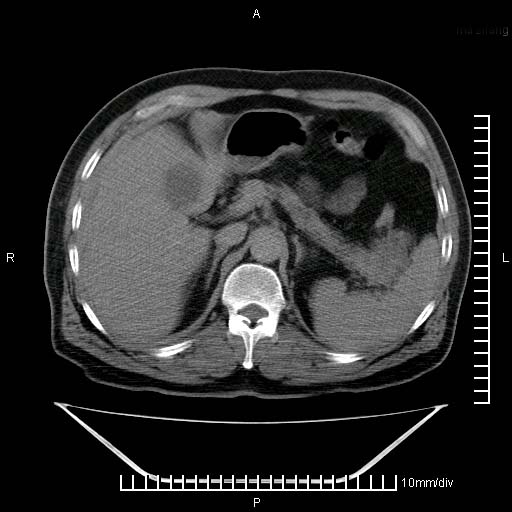

标题: CT25082:肝脏增强:男性,70岁 [打印本页]

标题: CT25082:肝脏增强:男性,70岁

患者以心脏疾病收住院,腹部无明显症状,b超查肝脏有占位。

牛眼征,中心坏死无强化,外缘强化,最外缘又见低密度,考虑转移,与脓肿鉴别

肝内多发转移瘤,右下肺炎症并少量胸水。胃壁增厚建议胃镜,胰尾部“病变”为肠管。

1)肝脏多发性转移瘤(不排除胰尾癌转移所致可能)。2)腹水。3)右侧少量胸腔积液。

ct25082 结果:转移瘤

外院mr结果:胰尾恶性占位。